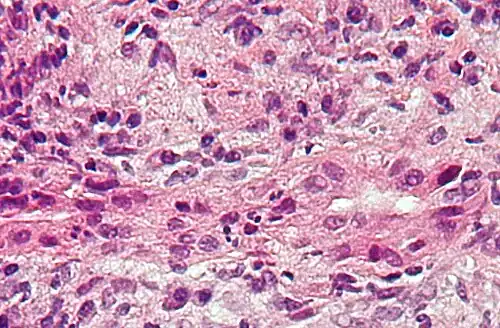

Low-magnification micrograph of PBC, H&E stain -

On microscopic examination of liver biopsy specimens, PBC is characterized by chronic, nonsuppurative inflammation, which surrounds and destroys interlobular and septal bile ducts. These histopathologic findings in primary biliary cholangitis include:[32]

- Inflammation of the bile ducts, characterized by intraepithelial lymphocytes

- Periductal epithelioid granulomas.

- Proliferation of bile ductules

- Fibrosis (scarring)

The Ludwig and Scheuer scoring systems have historically been used to stratify four stages of PBC, with stage 4 indicating the presence of cirrhosis. In the new system of Nakanuma, the stage of disease is based on fibrosis, bile duct loss, and features of cholestasis, i.e. deposition of orcein-positive granules, whereas the grade of necroinflammatory activity is based on cholangitis and interface hepatitis. The accumulation of orcein-positive granules occurs evenly across the PBC liver, which means that staging using the Nakanuma system is more reliable regarding sampling variability.